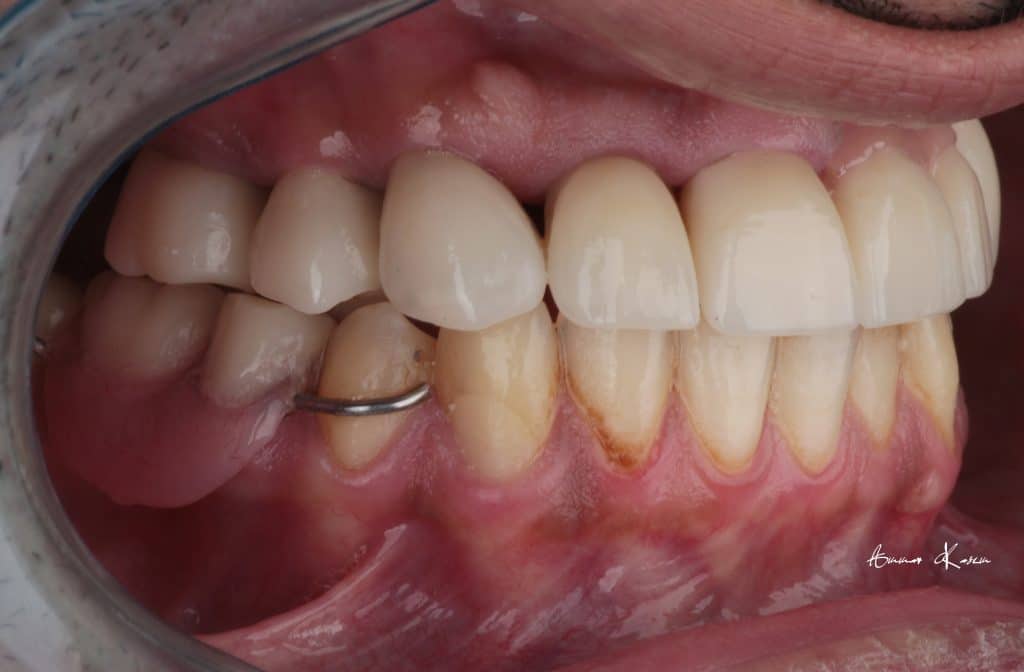

8- Ceramic fabrication including zirconia bridge and e.max crowns

9- Fabrication of RPD posteriorly till implant phase

6- 2nd mock up ( Normal class I) for 3 months